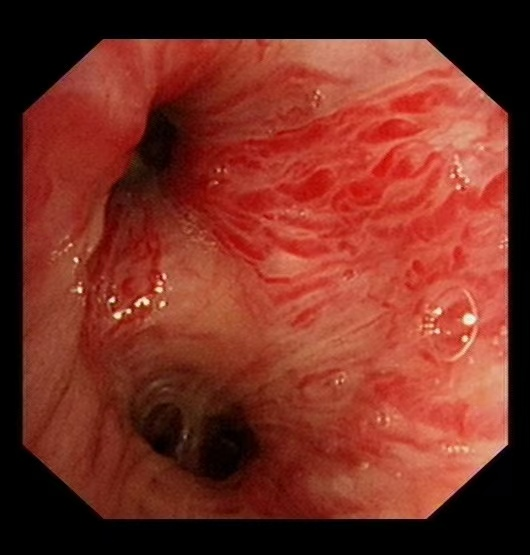

58歲的汪先生(化名)因大咯血入院,雖生命體征平穩,但出血癥狀持續未緩解。經支氣管鏡檢查發現,其左側支氣管內存在浸潤性新生物,表面血管扭曲、血供豐富,隨時可能再次出現大咯血,病情十分兇險。

“支氣管淀粉樣變發病率極低,極易誤診漏診!”我院呼吸與危重癥醫學科副主任(主持工作)王開金副主任醫師介紹,該病由淀粉樣物質異常沉積于氣道引發,臨床表現缺乏特異性,確診必須依賴病理活檢?!按死颊叱鲅L險極高,活檢操作猶如‘刀尖起舞’。”王開金表示,團隊通過血管介入止血、支氣管鏡精準定位和快速病理檢測,實現了“診斷-治療”一體化,為患者搶得生機。